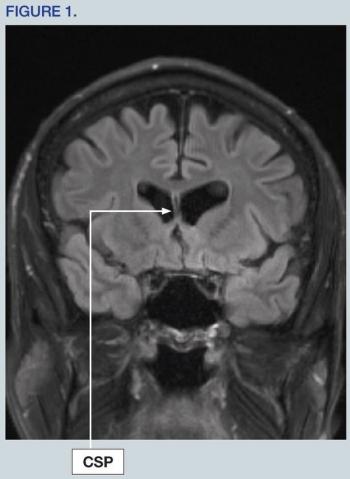

A 59-year-old man with a history of multiple concussions has been having a series of neurocognitive symptoms for the past several years. Discover more in this case.